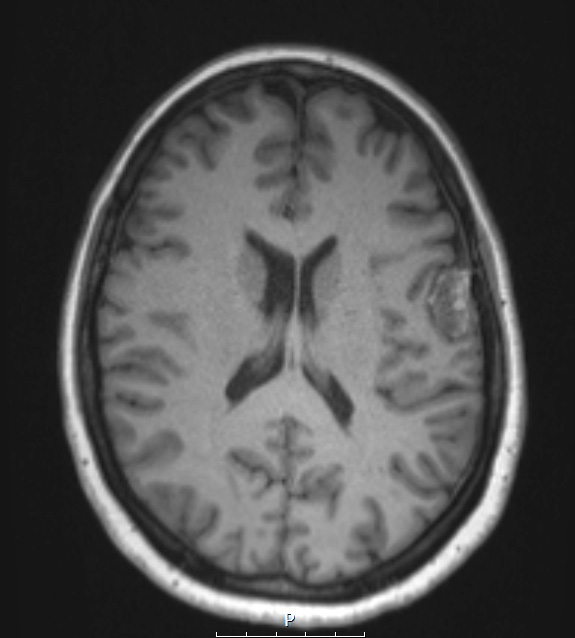

17A2,3 This T1-weighted image shows a patchy hyper- and isointense tumor mass without contrast (17A2) which enhances with contrast (17A3).